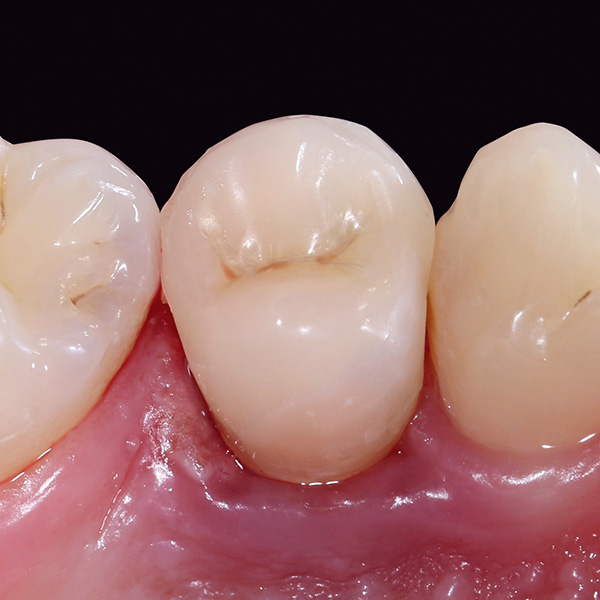

VITA ENAMIC multiColor Endokrone: Ausgangssituation vs. Finales Ergebnis

Ergebnis: VITA ENAMIC multiColor integrierte sich harmonisch in die natürliche Zahnsubstanz. Die insuffiziente Kompositfüllung an Zahn 14 (od) hatte zu Entzündungen im Zahnzwischenraum geführt.